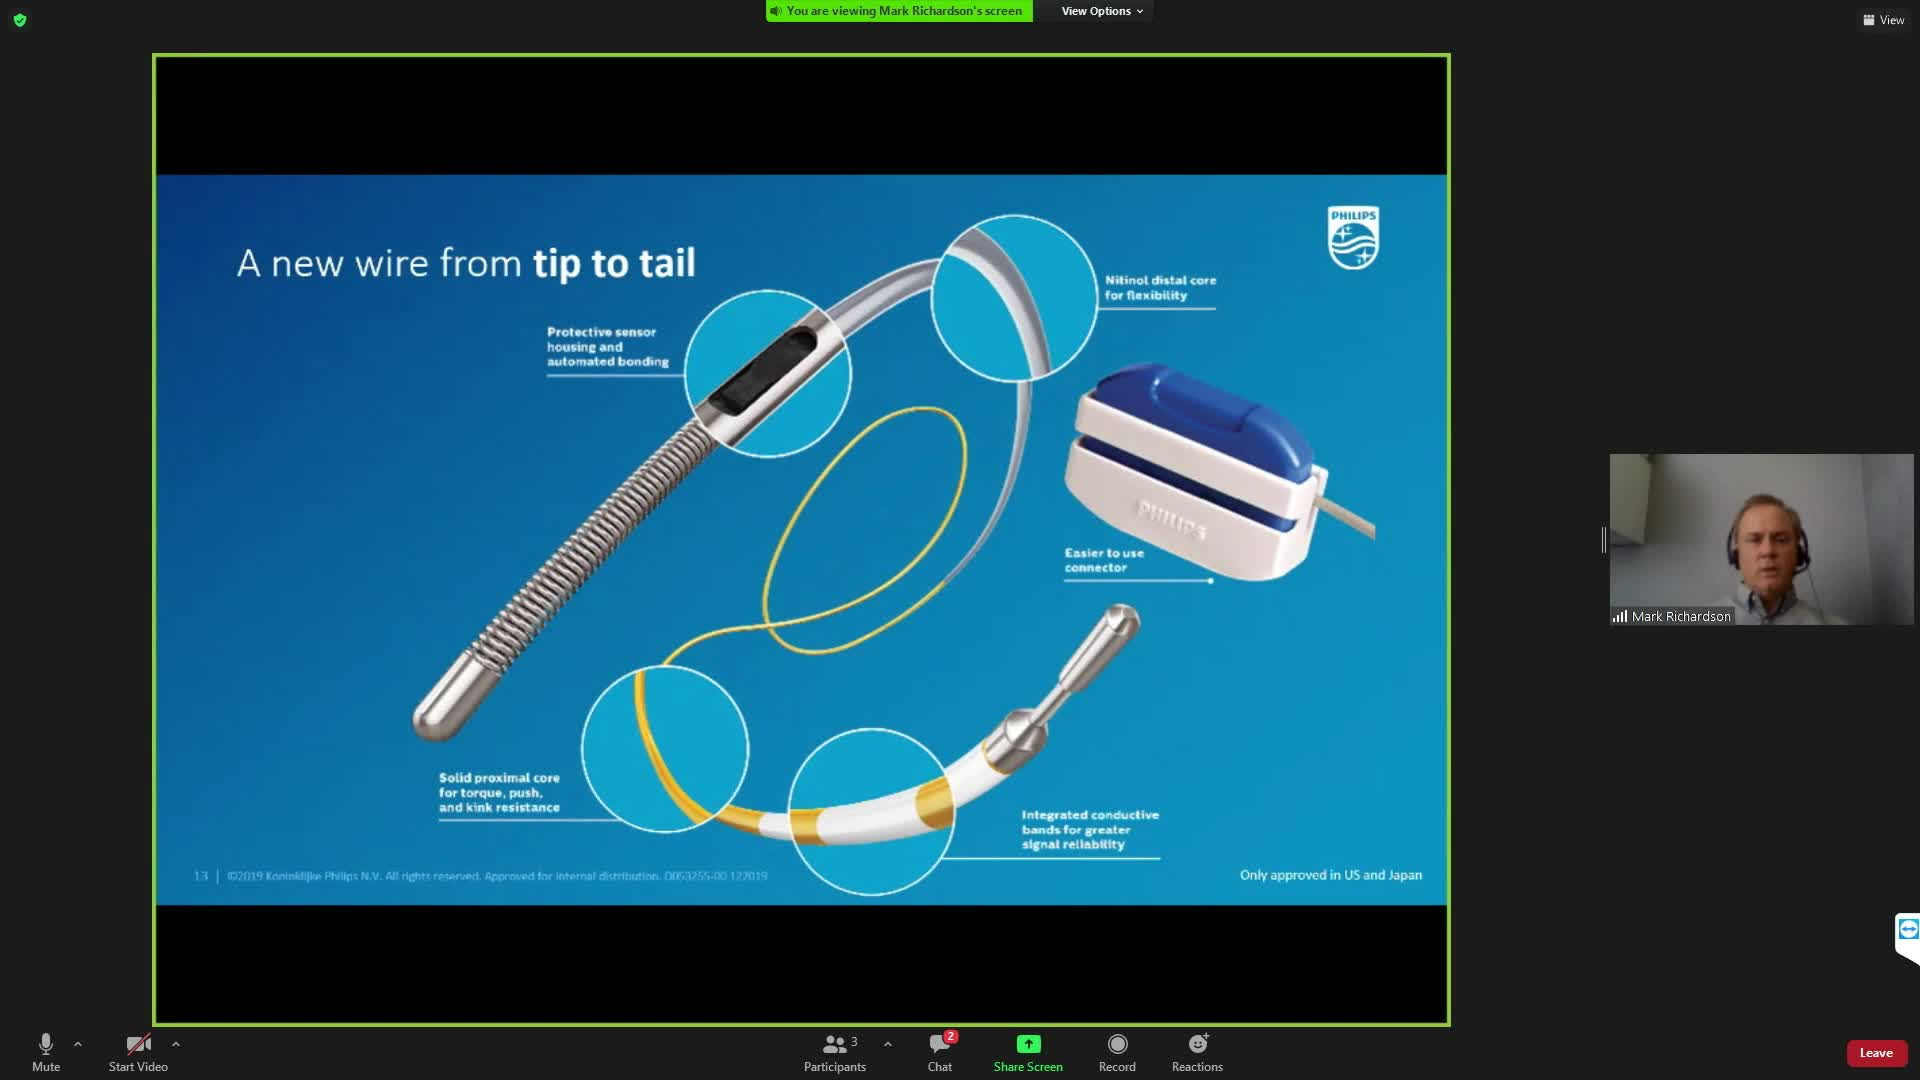

Understanding how SyncVision differs from other co-registration based technologies - Dr Justin Davies